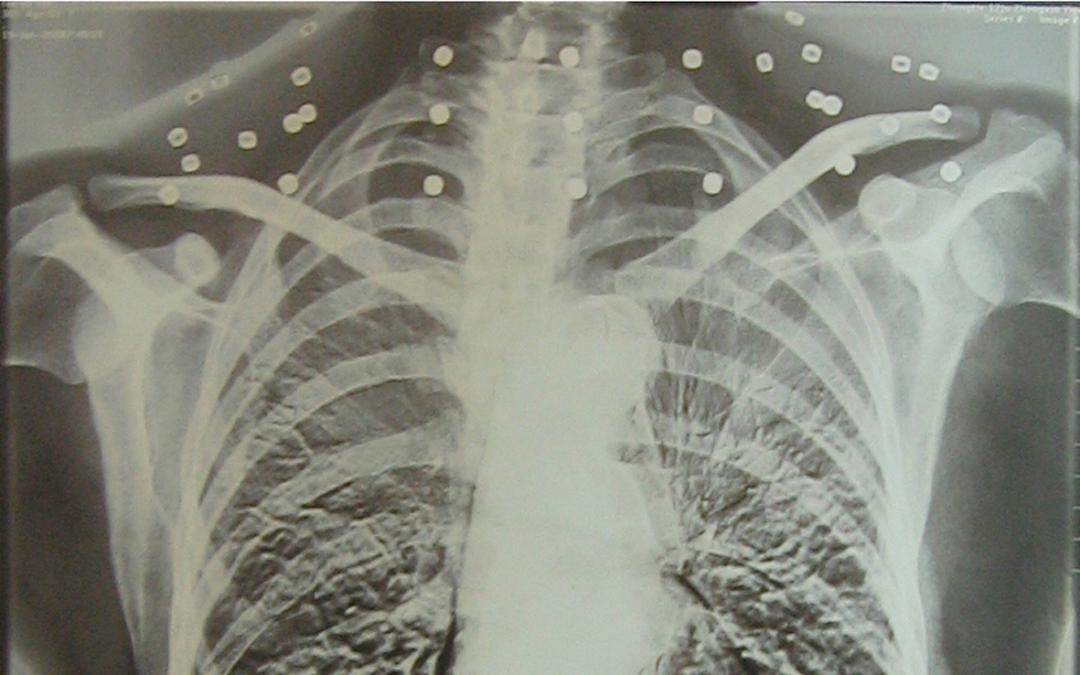

這張照片

是今年82歲的吳以先老人

拍攝的一張CT照

但實際上是

吳以先的頸部和腹部

共分佈着33枚彈片

但是打進身體裏的彈片

一直留在了體內

他體內的彈片都沒有取出

但吳以先不考慮取出彈片

在他看來

這是他與戰友並肩作戰的見證

是他的勳章